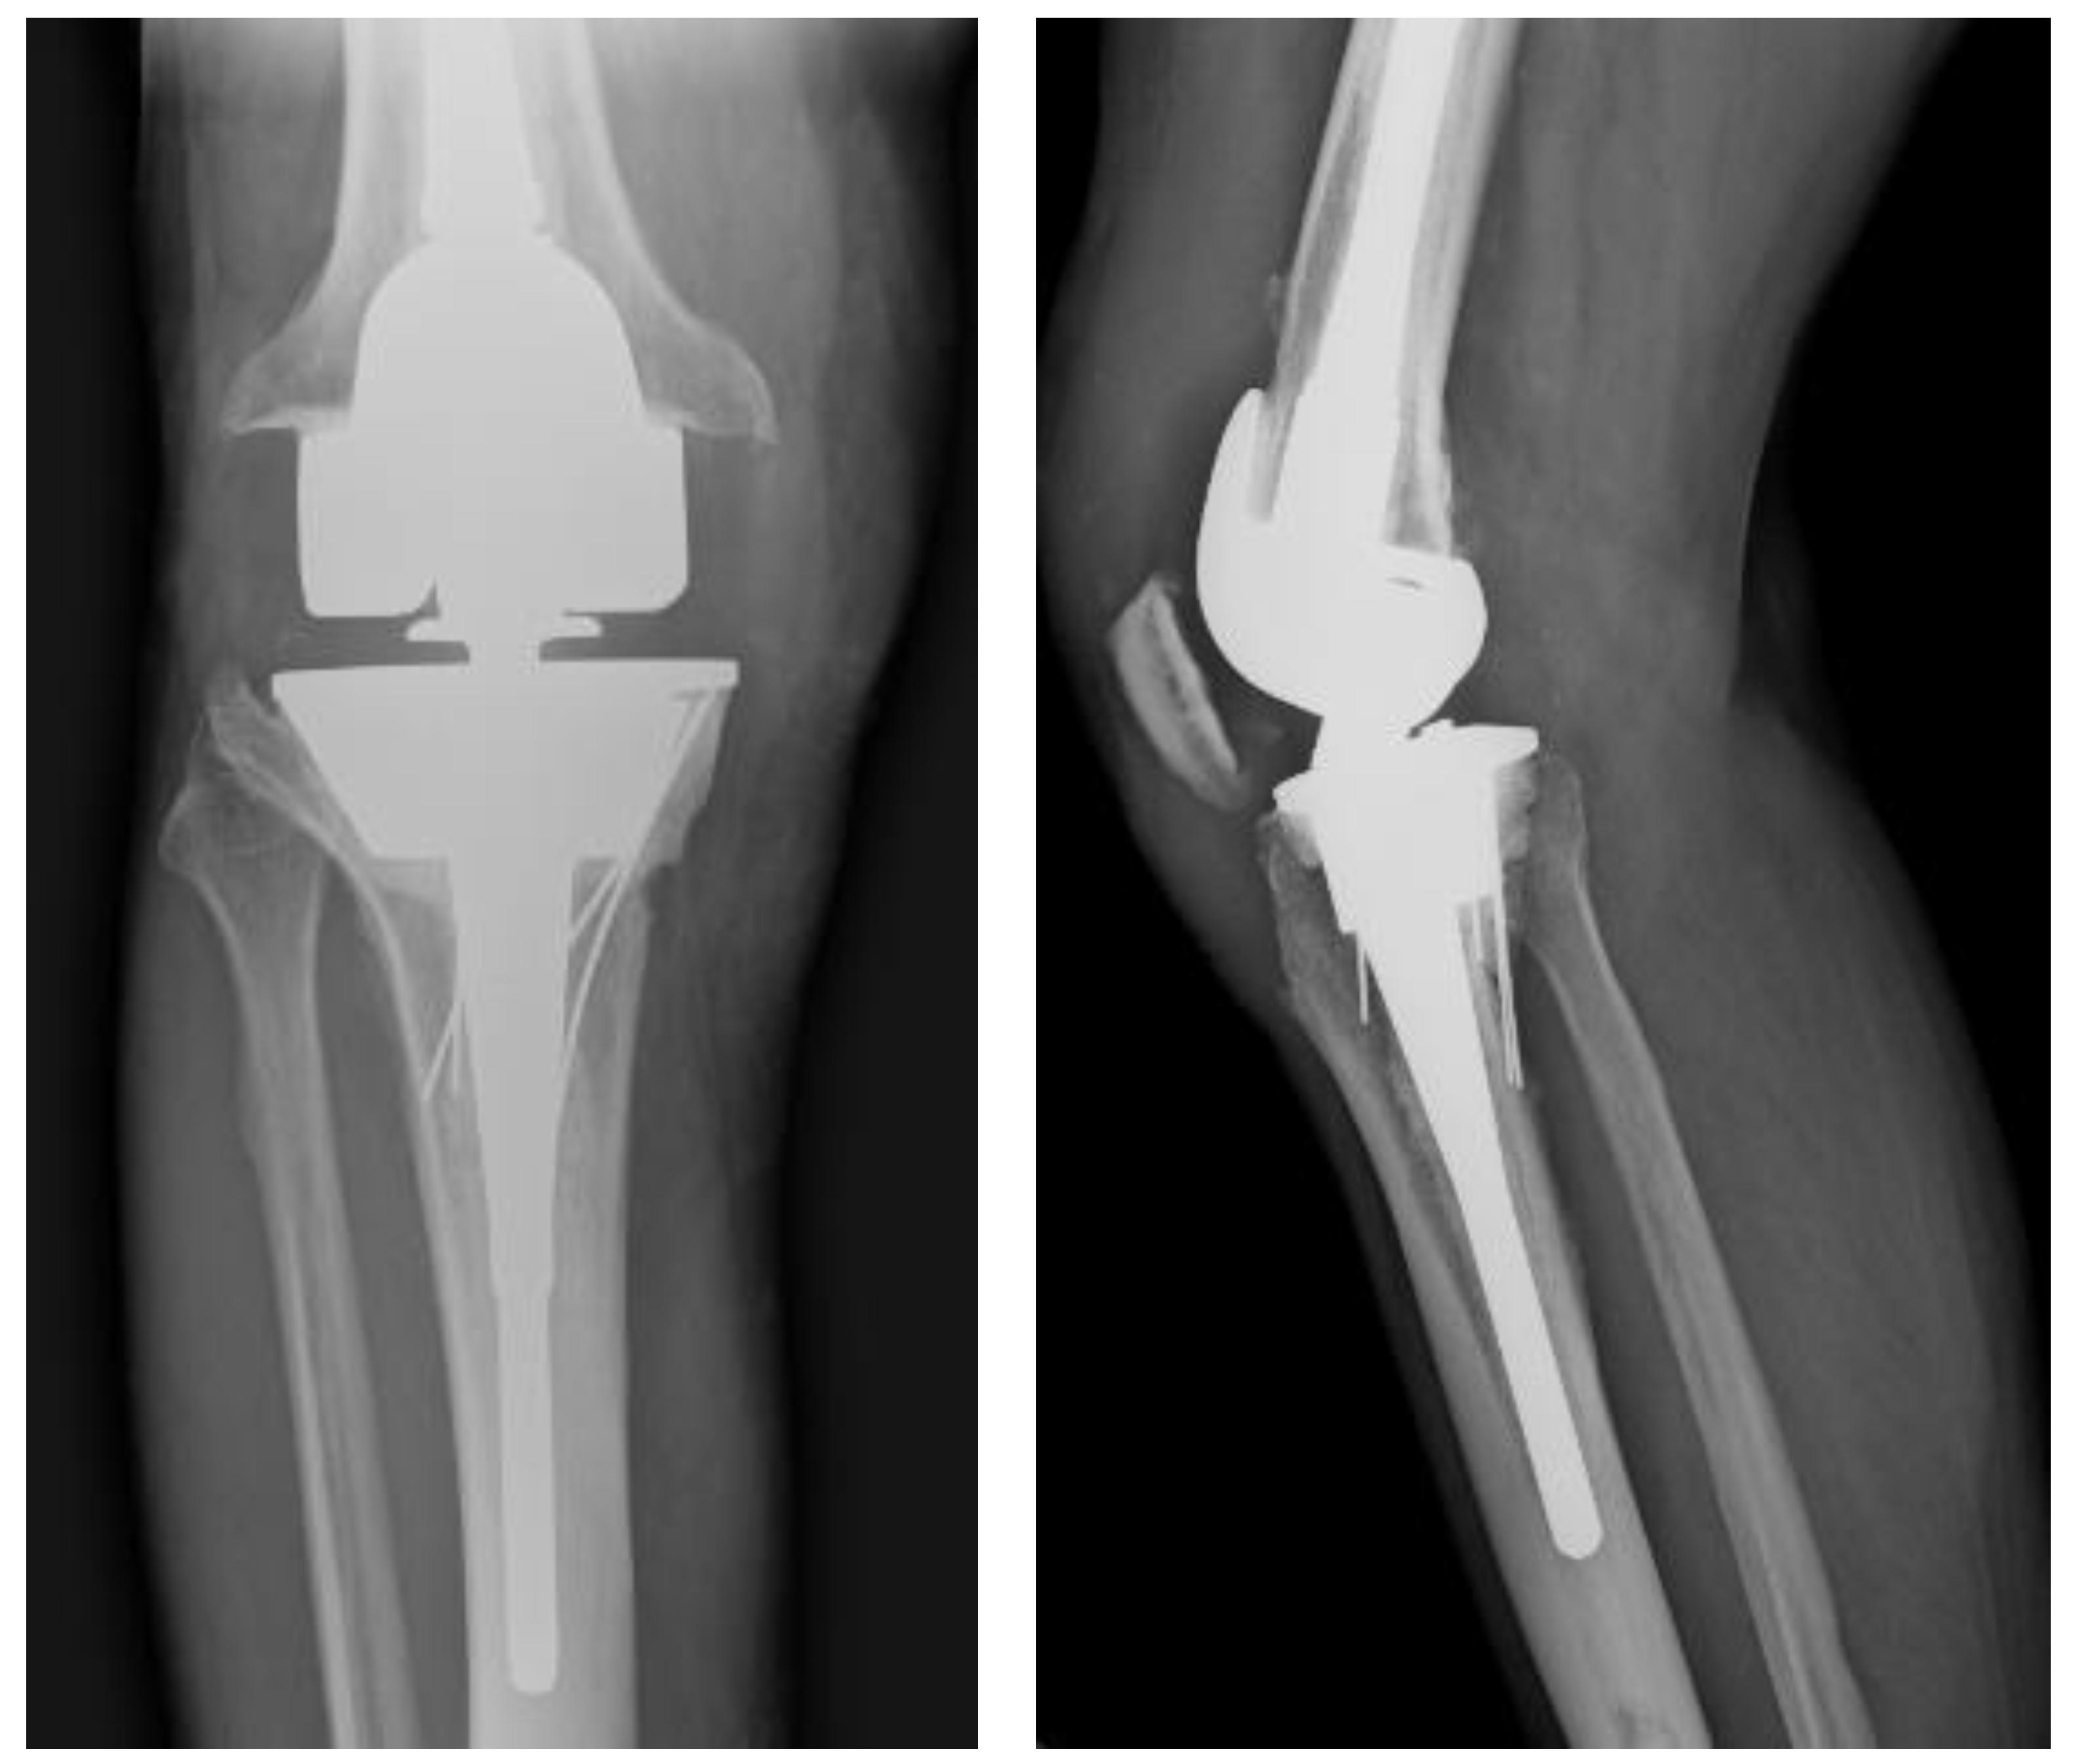

2. Case Description